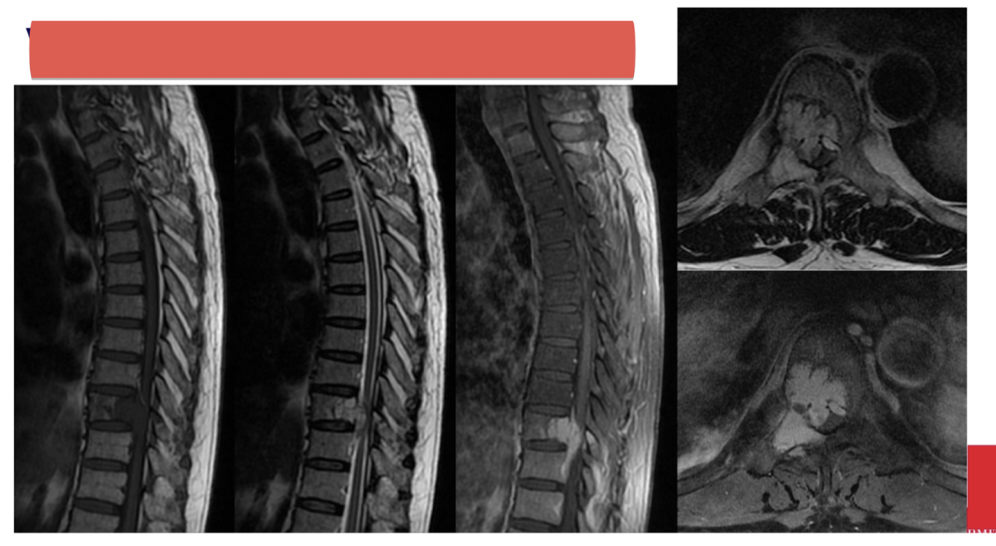

Sequences + pathology?

• T1, STIR, T1FS C+

• Sarcoma within the muscle of the right thigh

• T1 – lacking symmetry between the left and right thigh

• STIR – fluid sensitive scan that has picked up fluid involvement hence,

suggestive of a pathological process.

• T1FS C+ - vascular involvement has there is high signal from contrast

situated inside the sarcoma.

Pathology?

• Vertebral tumour that has invaded the spinal cord